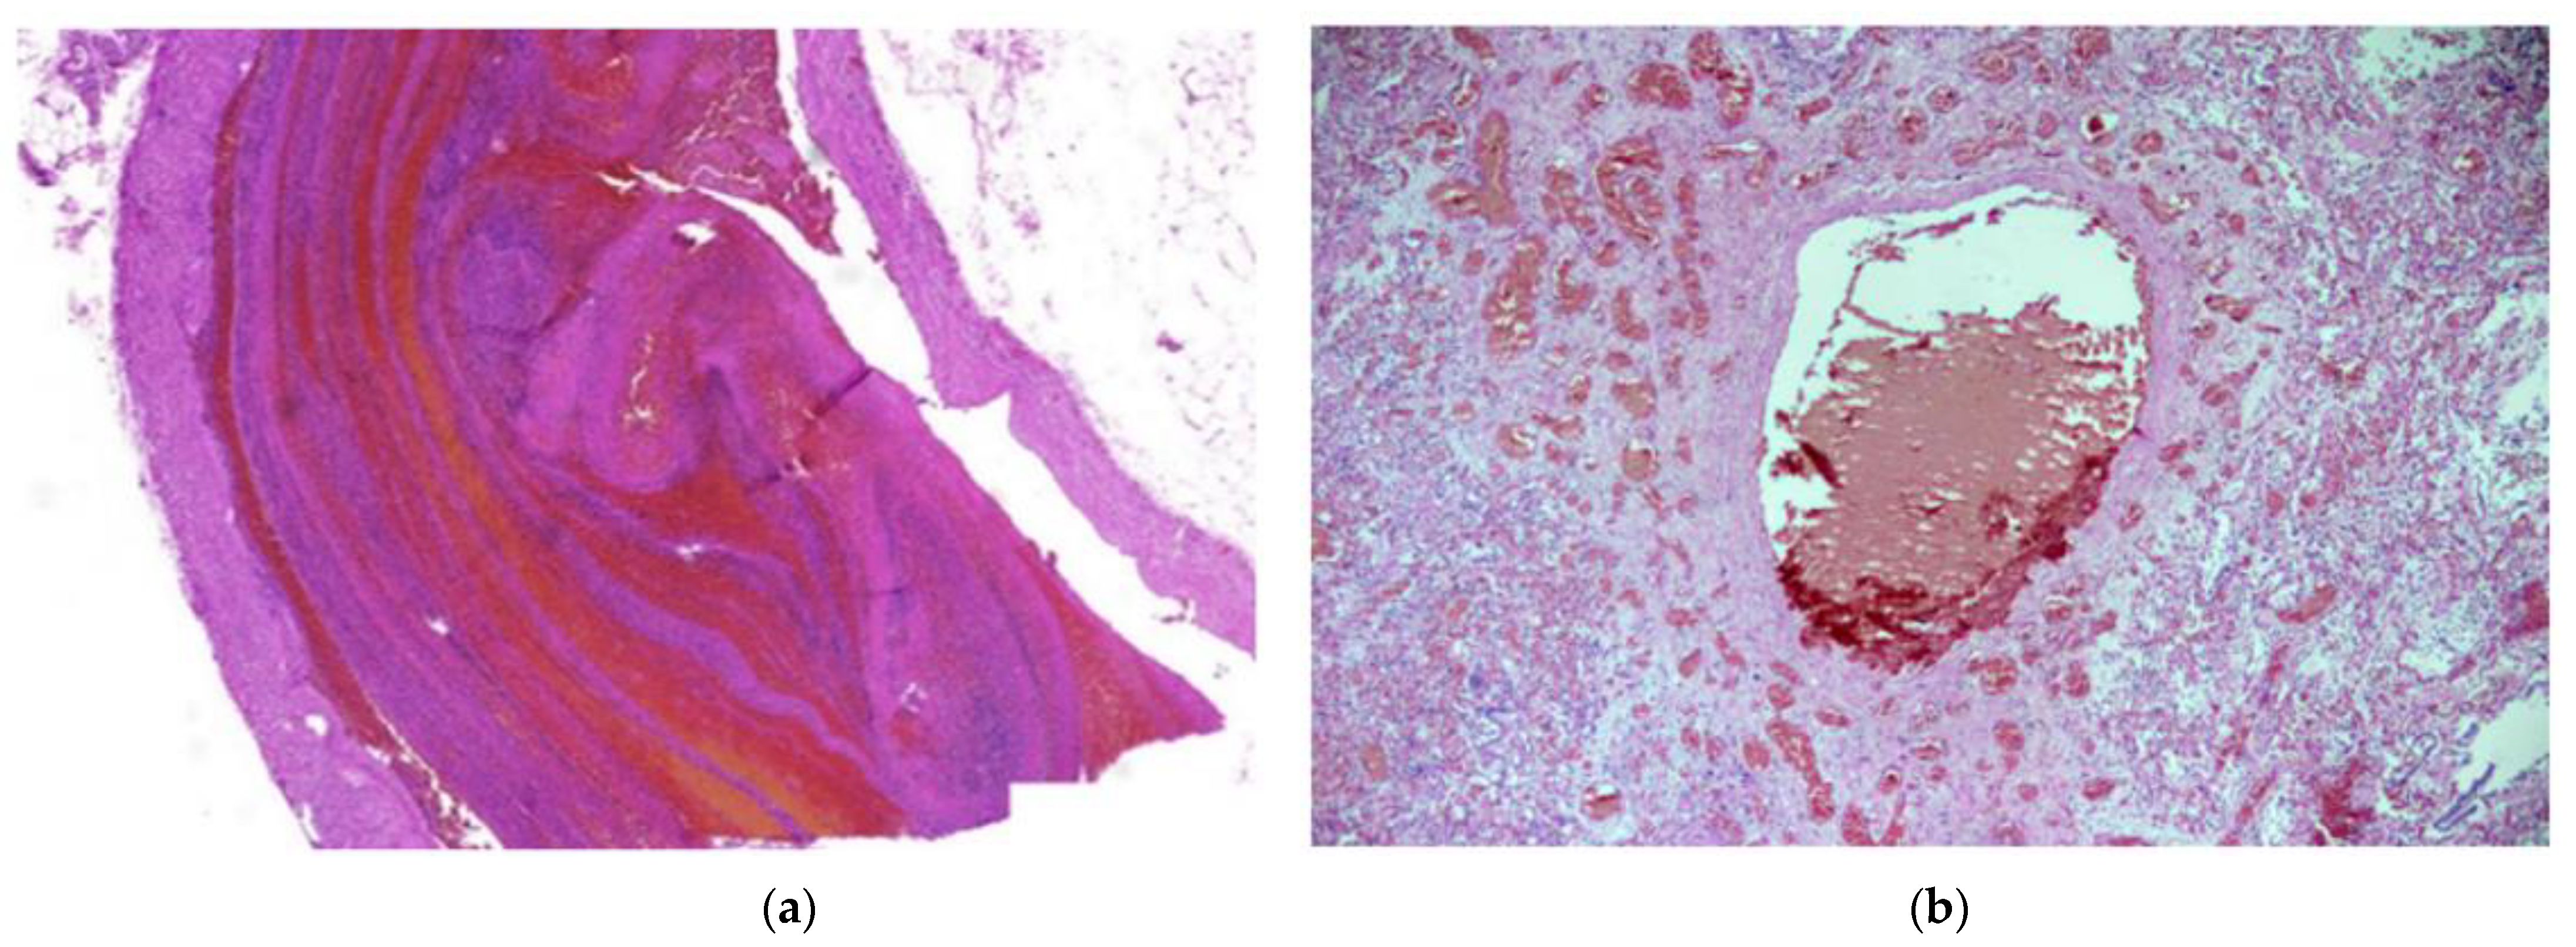

Histologically, 83/88 (94.3%; 95% CI 87.0–97.9) of patients had diffuse alveolar damage (DAD). Of these, 38/88 (43.2%; 95% CI 33.3–53.6) were in the exudative phase, as evidenced by collapsed alveolar structures, pneumocyte desquamation, hyaline membranes, and a sparse inflammatory infiltrate (Figure 1a). Patients totaling 45/88 (51.1%; 95% CI 40.8–61.3) of cases had DAD in the proliferative phase, as characterized by the presence of interstitial and intra-alveolar fibrosis, a sparse inflammatory infiltrate with more macrophages and a lack of hyaline membranes. Vascular damage was identified in 70/88 (79.5%; 95% CI 69.9–86.7) of cases, as evidenced by intra-alveolar hemorrhage and micro thromboembolism (Figure 1a and Figure 2b). Small, medium and large caliber vessel thromboses were identified in 83/88 (94.3%; 95% CI 87.0–97.9) of cases, with 12/88 (13.6%; 95% CI 7.8–22.5) of patients having developed a pulmonary embolism (PE) (Figure 2a,b). Hemorrhagic infarctions were identified in 27/88 (30.7%; 95% CI 22.0–41.0) of patients.

Figure 1. (a) Diffuse alveolar damage, exudative phase. Hyaline membranes (yellow arrow) and a sparse inflammatory infiltrate with mostly macrophages and lymphocytes are seen. Capillary thromboses (blue arrows) and some hemorrhaging are also visible. H & E stain; magnification ×40. (b) Diffuse alveolar damage, proliferative phase. Alveolar walls are thickened, and fibrous polyps can be seen in the lumen of alveoli (blue arrows). H & E stain; magnification ×100.

Figure 2. (a) Pulmonary thrombosis. An elongated thrombus filling almost the entire lumen of an artery can be seen. H & E stain; magnification ×30. (b) Thrombus in a large vessel with smaller vessel thromboses surrounding it. H & E stain; magnification ×40.